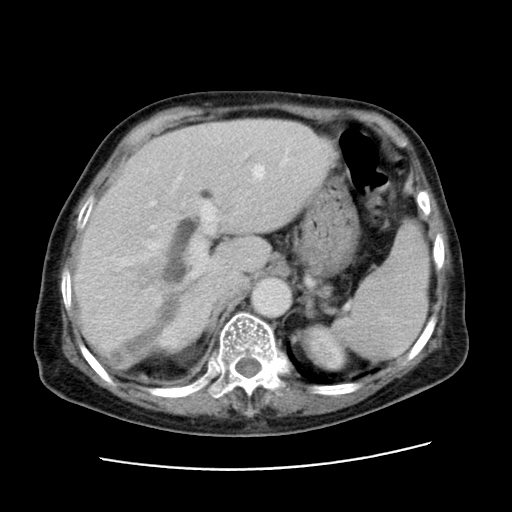

女,77.无不适

肝脏变异、异位胆囊,肝右叶肝内胆管结石并肝内胆管扩张。

肝右叶肝内胆管结石并肝内胆管扩张。

肝右叶肝内胆管结石并肝内胆管扩张

胆总管扩张

肝右叶肝内胆管结石并肝内胆管扩张。胆总管下段梗阻,考虑壶腹部占位。

右侧肝内胆管局限性扩张,其内密度不均匀,扩张的胆管壁增厚,考虑肝内胆管炎合并结石可能性大